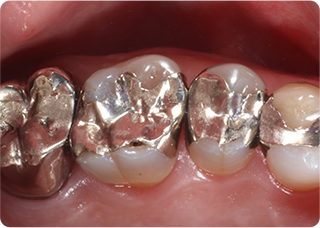

精密根管治療④

術後

| 主訴 | 奥歯で噛むと痛い |

| 治療期間/回数 | 1ヵ月、3回 |

| 価格(税込) | 88,000円(税込) |

| リスク・副作用 | 病変再発、歯根破折の可能性 |

| ポイント | う蝕検知液を用い、むし歯の取り残しが無いようにし、ラバーダム防湿を行い、無菌的に根管治療を行った。根管充填材は、殺菌作用の強い保険適応外のMTAセメントを使用した。 |